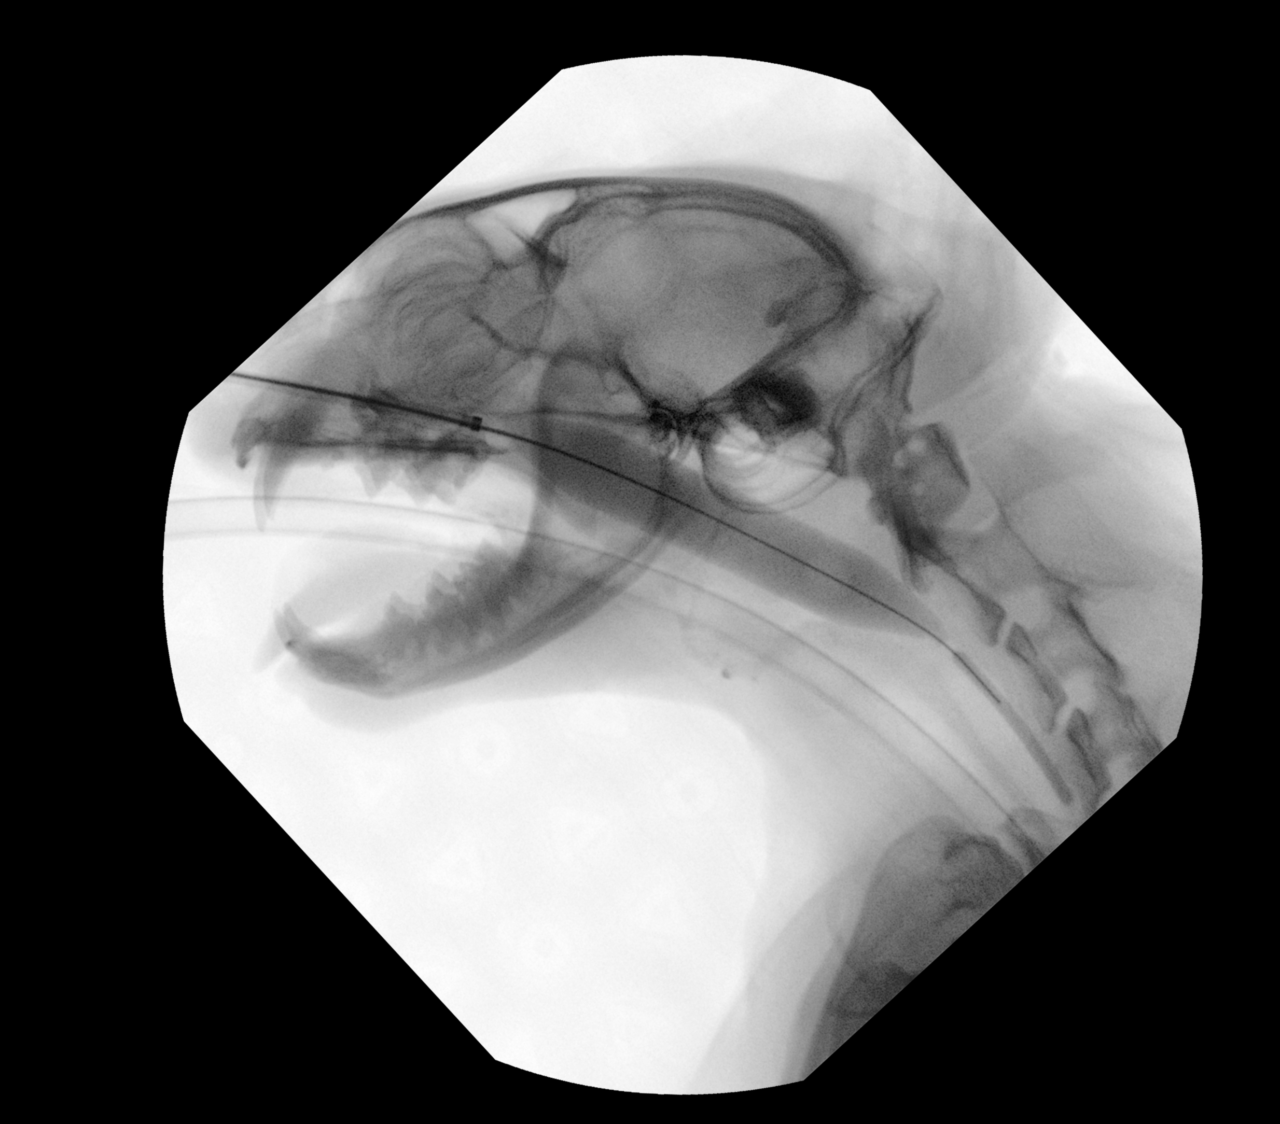

猫の鼻咽頭狭窄に対するバルーン拡張術

の鼻咽頭狭窄に対するバルーン拡張術(Balloon Dilation )は、非侵襲的な治療法としてよく利用される手法です。

バルーン拡張術の概要は、バルーンカテーテルを用いて狭窄部を拡張し、通気を改善する治療法です。適応症例としては内科治療(抗炎症剤、抗生剤)で改善しない鼻咽頭狭窄です。エックス線透視装置を用いて、狭窄部位にバルーンを誘導し、拡張、一定時間(15分程度)保持します。※今回は7気圧で拡張